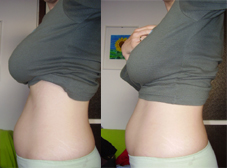

pocak 10+0

pocak 10+0